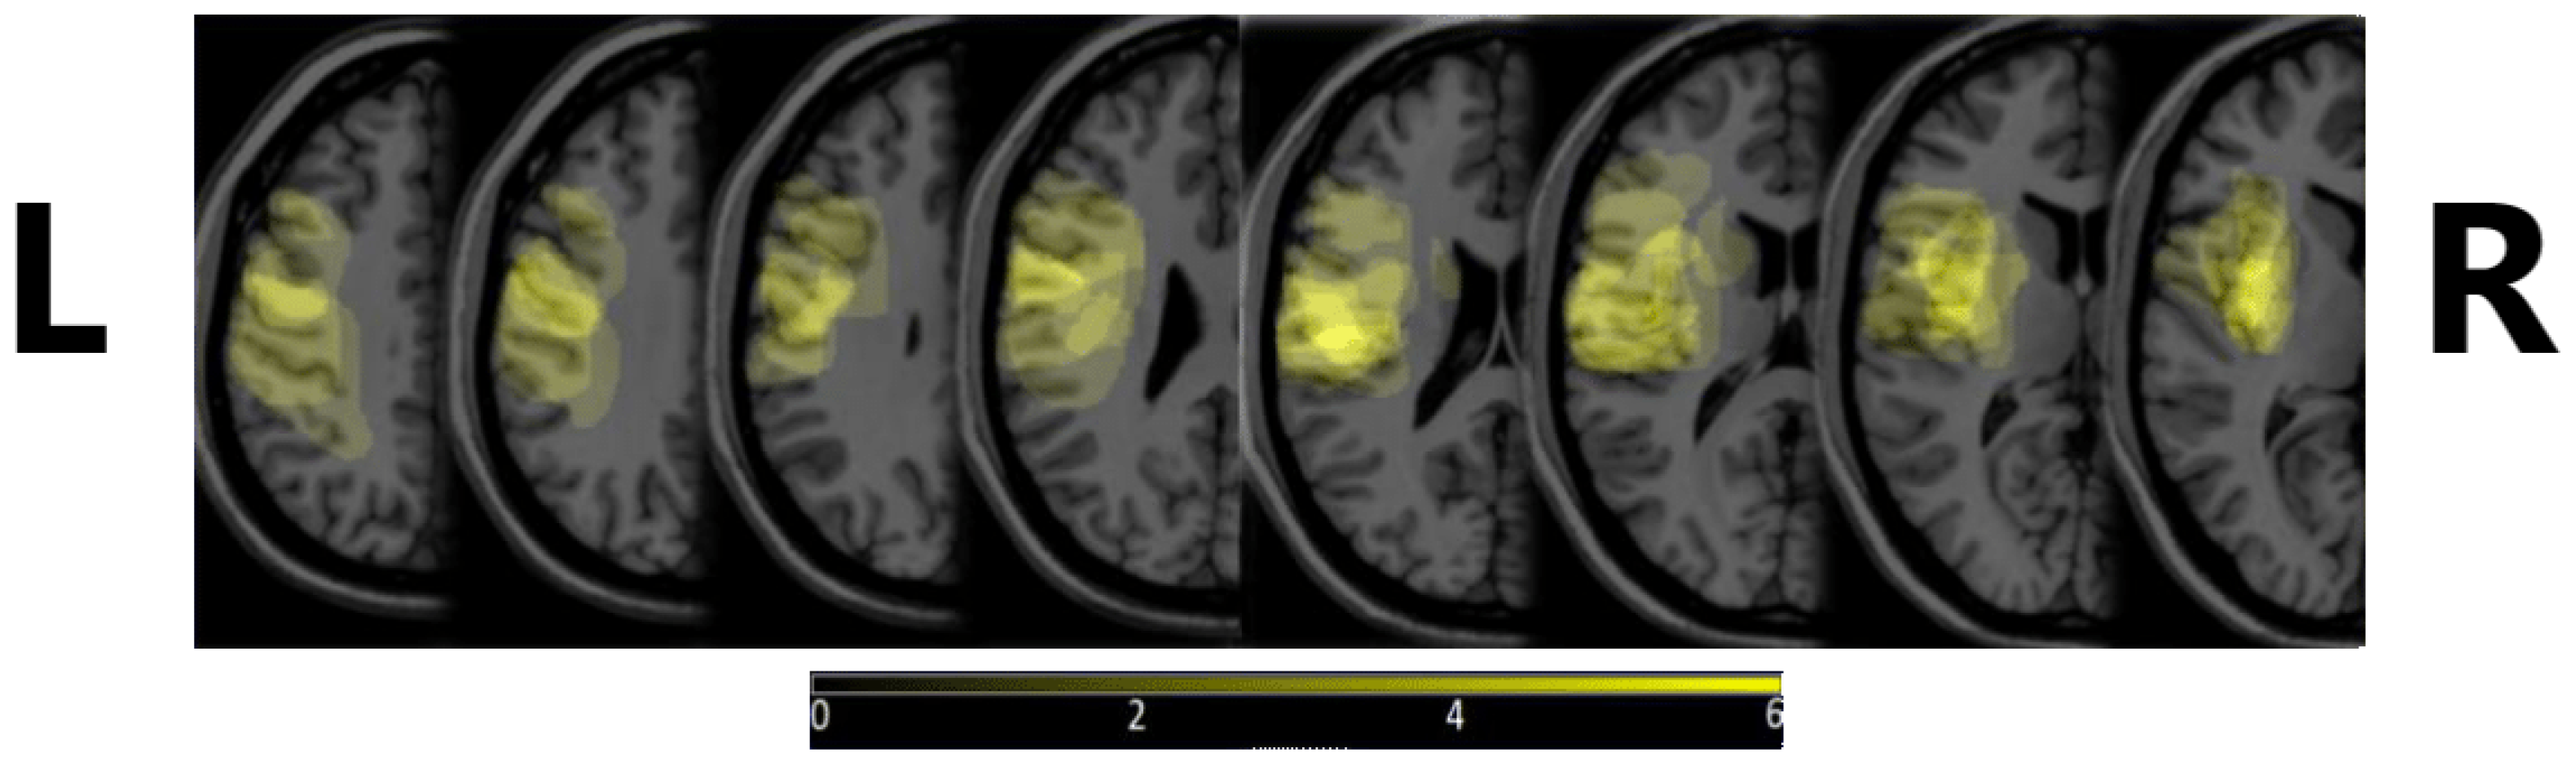

The 10 patients were selected based on the Boston Diagnostic Aphasia Evaluation (BDAE) and right-handedness based on Edinburgh Handedness Inventory (EHI), their age ranged from 47 to 85, and they were, on average, 67 years of age [21]. Additional inclusion criteria were that the stroke that the patient experienced was their first one, it occurred in the territory of the M2 segments of the left middle cerebral artery, and an observable lesion was present in Broca’s area or its vicinity, or in part of Broca’s complex. The exclusion criteria were the presence of a known psychiatric or neurological disorder prior to stroke, moderate to severe hemiparesis, severe complications or worsening of the patient’s condition, more than a single stroke, or the presence of other intracranial pathologies (e.g., tumor or vascular leucopathy). Figure 1 shows the density map of the lesions, depicting where these were most commonly observed. MRIcron v. 8/2014 was used to create the image, from diagnostic MRI images.

Figure 1. Lesion density maps for our subjects. A more intense yellow color denotes the more frequent occurrence of a lesion in that area. The brightest yellow shows that 6 or more subjects had a lesion there. L and R letters denote the left and right side of the head, respectively, to avoid confusion with MRI image display conventions.